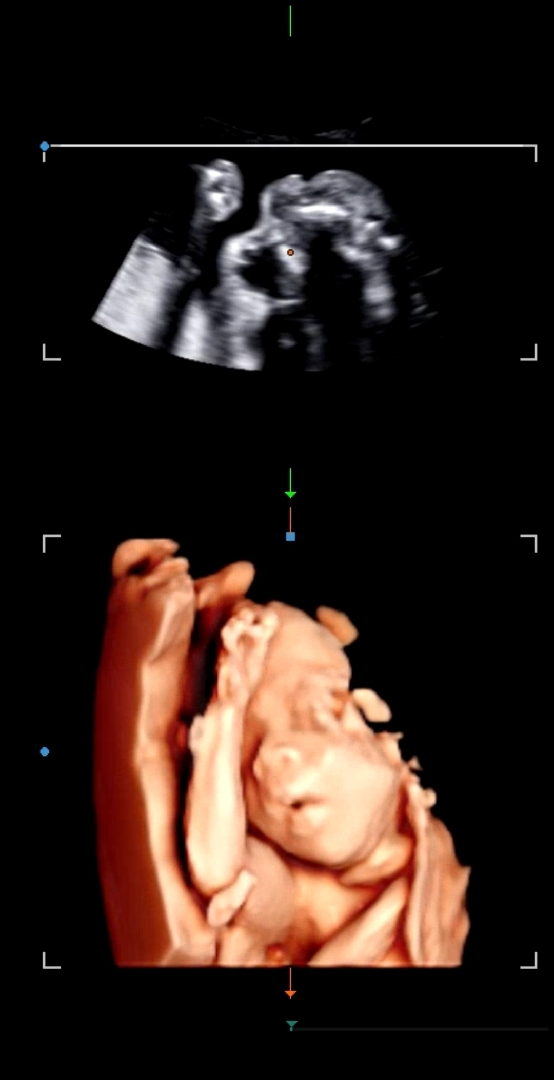

23주차 때 입벌리고 있는게 너무 귀여워요

지금은 26주차인데 23주차때 찍은 초음파에 입모양, 얼굴 가리고 있는 한쪽 팔 그 아래 팔뚝살까지 귀여운 포인트가 너무 많아서 생각날 때 마다 보고있어요😍